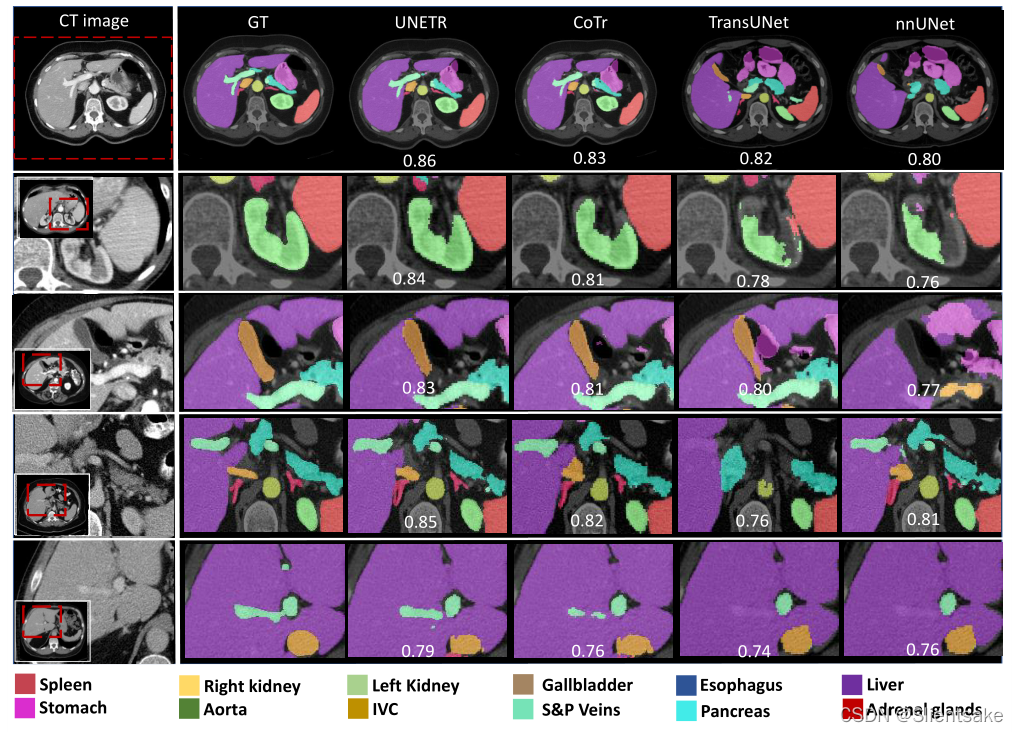

多器官分割的定性比较如图3所示。UNETR提高了腹部器官的分割性能。模型学习远程依赖的能力在第3行(从上面开始)很明显,其中nnUNet混淆了肝脏和胃组织,而UNETR成功地描绘了这些器官的边界。在图3中,第2行和第4行显示肾脏和肾上腺对周围组织的清晰检测,这表明UNETR捕获了更好的空间上下文。与基于二维Transformers的模型相比,UNETR展示了更高的边界分割精度,因为它准确地识别了肾脏和脾脏之间的边界。可见胆囊在第二排,肝脏和胃在第三排,门静脉对肝脏在第五排。在图4中,给出了在MSD数据集上对脑肿瘤分割的定性分割比较。具体来说,模型在捕捉肿瘤的细粒度细节方面表现得更好。

图3:BTCV交叉验证中不同基线的定性比较。第一行为完整代表性CT切片。展示了4个放大的受试者(第2至5行),方法显示了肾脏和脾脏(第2行)、胰腺和肾上腺(第3行)、胆囊(第4行)和门静脉(第5行)的分割效果。每个样本上显示了受试者的平均Dice得分。

在所有数据集的实验表明,UNETR的性能优于CNN和基于Transformers的分割模型。具体来说,UNETR通过捕获全局和局部依赖实现了更好的分割精度。在定性比较中,这一点在各种案例中得到了说明,在这些案例中,UNETR有效地捕捉了长期依赖关系(例如图3中对胰腺尾部的精确分割)。

此外,UNETR在BTCV排行榜上的细分表现显示了新的最先进的基准,并验证了其有效性。特别是对于小的解剖,UNETR优于CNN和基于Transformers的模型。虽然3D模型已经证明了对小器官(如胆囊、肾上腺)的高分割精度,但UNETR仍能以显著优势领先于最佳竞争模型(见表1)。

这在图3中也可以观察到,其中UNETR对左肾上腺和右肾上腺的分割精度明显更好,而且UNETR是唯一正确检测肾上腺分支的模型。对于较具挑战性的组织,如第4行胆囊和第5行门静脉,它们与周围肝组织的对比度较低,UNETR仍然能够分割出清晰的连接边界。